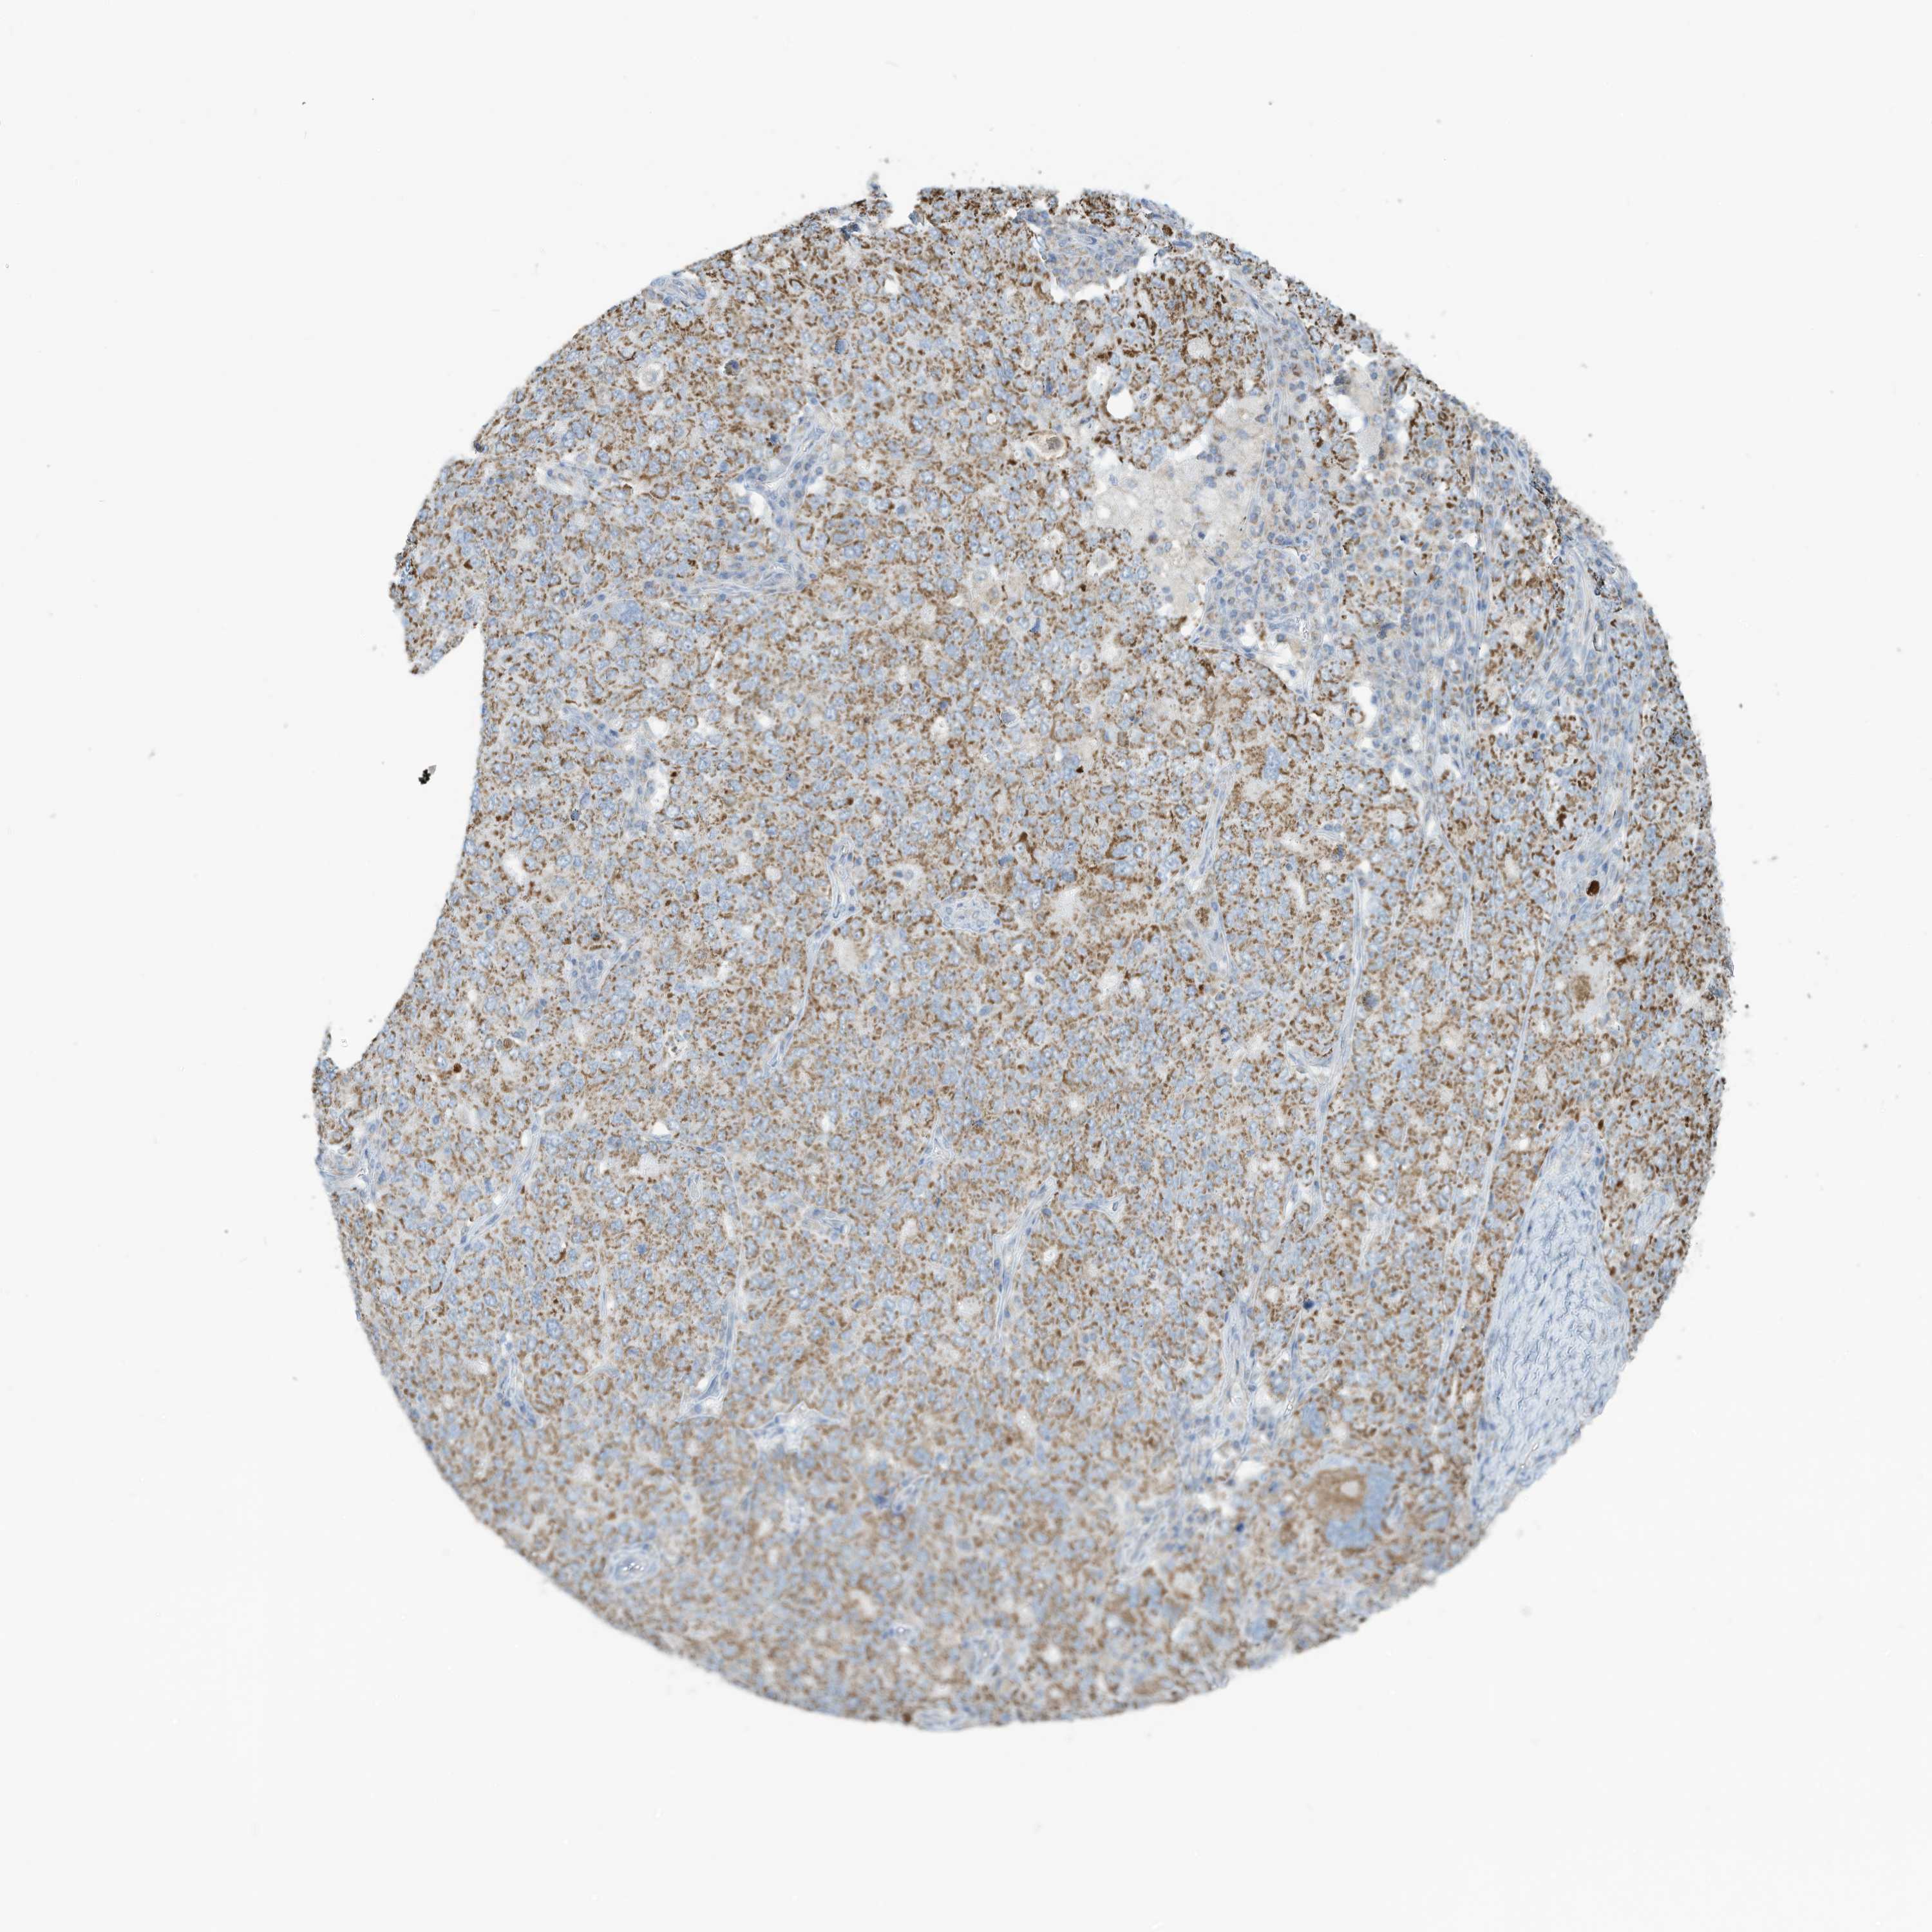

OVARIAN CANCER - Protein expressioni

A mouse-over function shows sample information and annotation data. Click on an image to view it in a full screen mode. Samples can be filtered based on level of antibody staining by selecting one or several of the following categories: high, medium, low and not detected. The assay and annotation is described here.

Note that samples used for immunohistochemistry by the Human Protein Atlas do not correspond to samples in the TCGA dataset.

Antibody stainingi

Antibody staining in the annotated cell types in the current human tissue is reported as not detected, low, medium, or high, based on conventional immunohistochemistry profiling in selected tissues. This score is based on the combination of the staining intensity and fraction of stained cells.

Each image is clickable and will lead to virtual microscopy that enables deeper exploration of all samples and also displays staining intensity scores, fraction scores and subcellular localization as well as patient and tissue information for each sample.

Antibody HPA031862

Staining

High

Medium

Low

Not detected

Intensity

Strong

Moderate

Weak

Negative

Quantity

>75%

75%-25%

<25%

None

Location

Nuclear

Cytoplasmic/membranous

Cytoplasmic/membranous,nuclear

Cystadenocarcinoma, serous, NOS